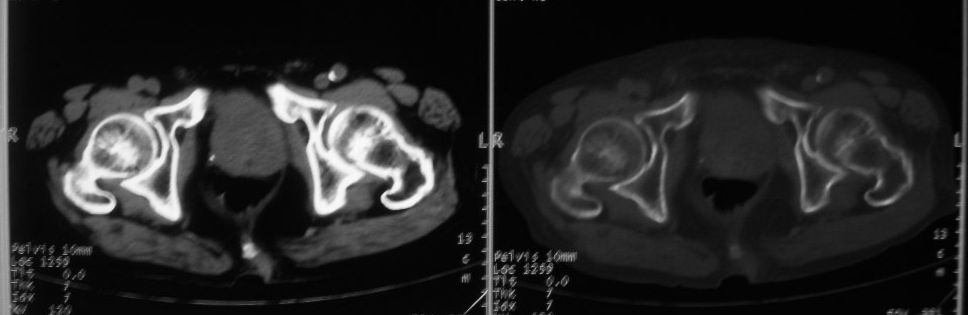

以下是引用zjzjr在2008-10-3 12:59:00的发言:[br]前列腺癌伴左髂骨\\腰椎转移可能性大.

以下是引用卜一在2008-10-3 13:40:00的发言:[br]前列腺癌!左髂骨\\腰椎转移?建议行全身骨扫描!

以下是引用深泽交通医院在2008-10-3 15:33:00的发言:[br]前列腺实性增大伴分叶状,与包膜间隙境界不清;椎体松质区间结节样密度影,考虑:前列腺癌,并椎体成骨性转移